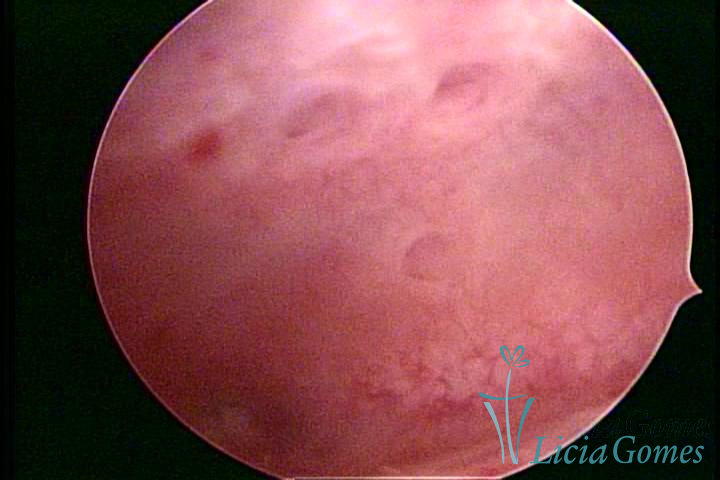

ADENOMIOSE

É a presença de tecido endometrial na camada muscular do útero

A vídeo-histeroscopia permite diagnosticar às lesões próximas às camadas miometriais superficiais, próximo ao endométrio visualizando lesões de coloração violácea, circunscritas, ou acastanhadas com conteúdo achocolatado.